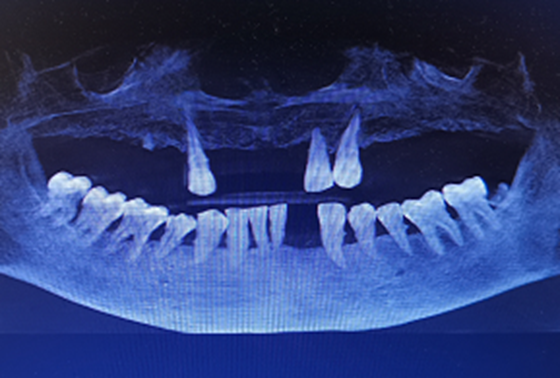

随着人们对牙齿的保护意识日益提升,医学技术的发达已经能够很好地解决牙缺失的难题,特别是数字化种植牙技术凭借着精准、快速、即种即用的优势成功帮助患者立长“新牙”。 术前CBCT显示牙根折断 湛女...